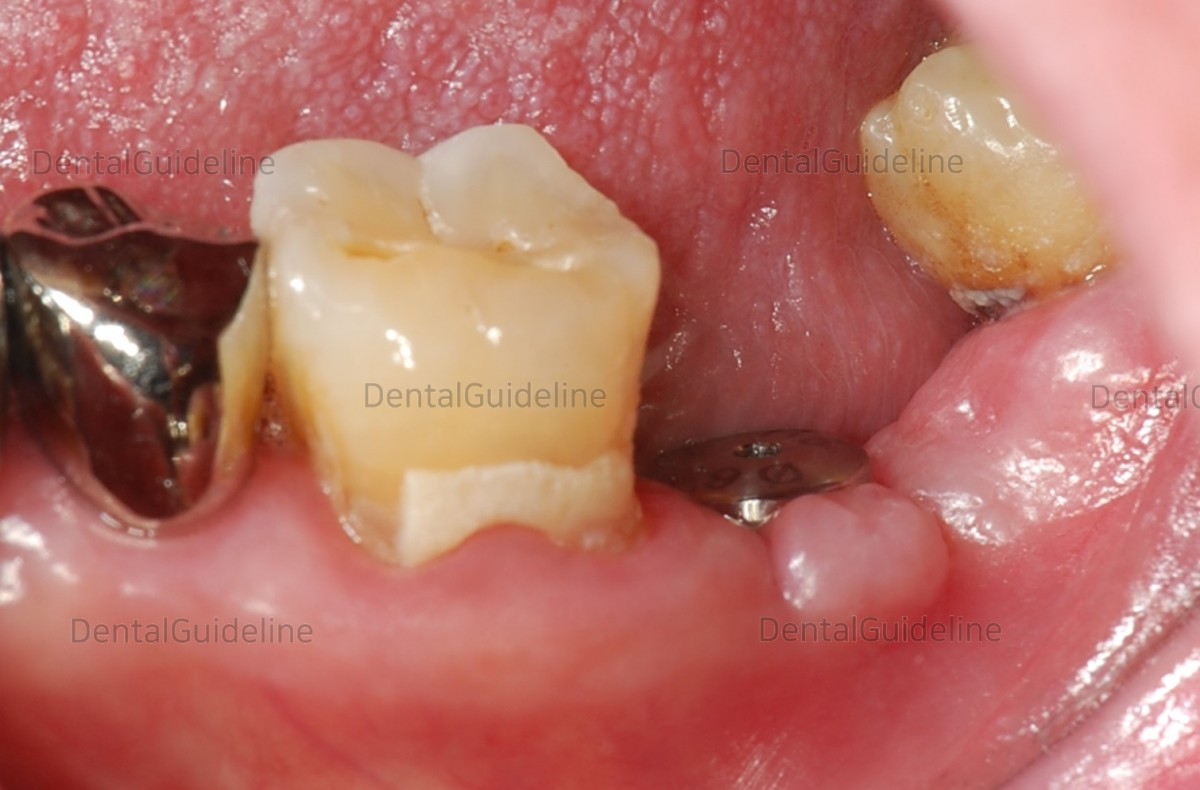

8 days after the surgery.